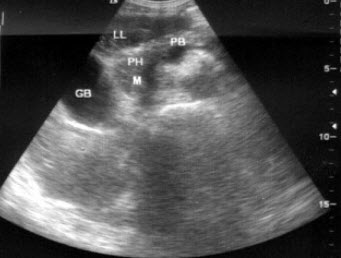

53、单项选择题

根据超声声像图,提示结构为()

A.脐带

B.胎盘

C.胎儿躯干

D.胎儿臀部

E.子宫肌层